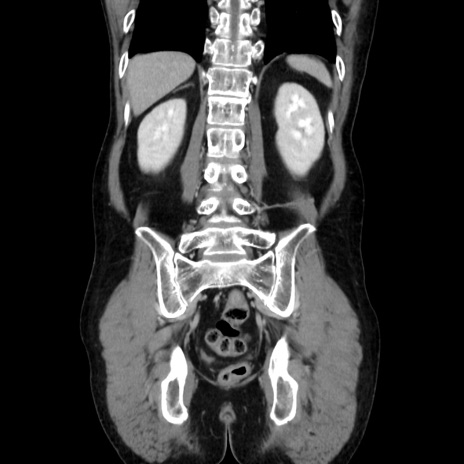

症例37(冠状断像)

【症例】40歳代 男性

【主訴】腹痛

【現病歴】4時間ほど前に電車に乗車中に臍部上より腹痛出現。徐々に増悪し起立困難となり、救急外来受診。生ものは数日食べていない。今朝お雑煮を食べた。

【身体所見】BT 36.8℃、BP 117/84mmHg、HR 91/min、SpO2 97%、苦悶様、腹部:臍上部広範囲圧痛あり、反跳痛±

【データ】WBC 8100、CRP 0.03